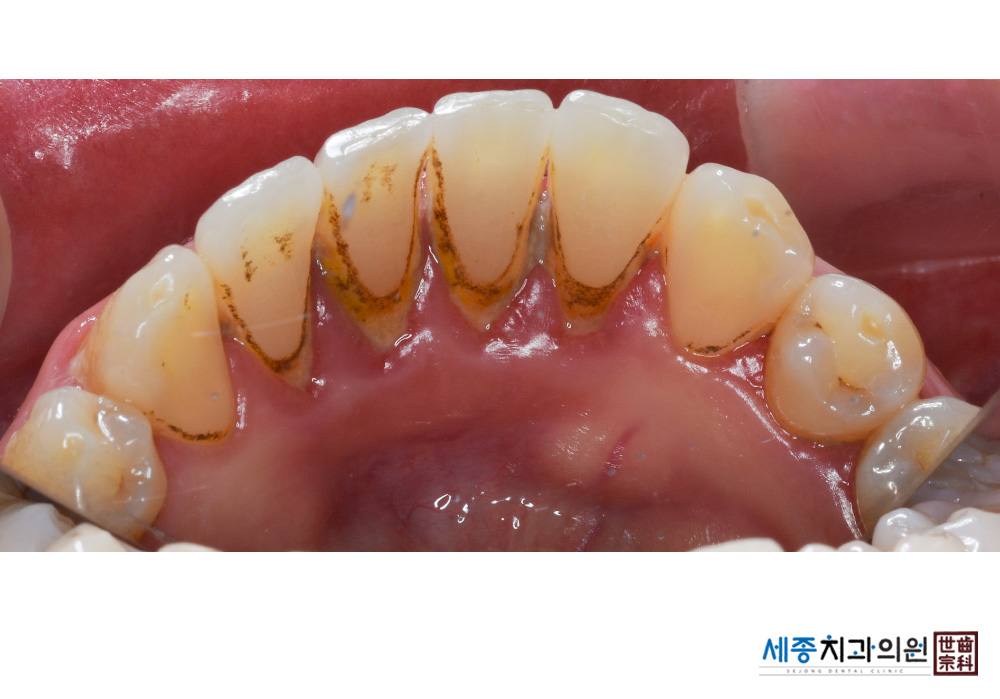

[스케일링] 치주질환 예방 스케일링 치료

치료전 : 2019-03-13

가글마취&저주파 스켈러를 사용한 스케일링